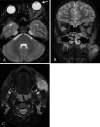

Kimura's disease (KD) is a rare, chronic inflammatory disorder, which is characterized by tumor-like masses mainly located in the head and neck region. Extraocular muscle involvement in KD is uncommon. We report a case of KD that involved both the extraocular muscles and buccal area. A 13-year-old male presented to our clinic with a two-year history of exophthalmos of the left eye and facial swelling. Facial CT and MRI showed a 1.5 x 1.5 cm(2) soft tissue mass located at the left masticator and buccal area, exophthalmos of the left eye, and diffuse thickening of the left extraocular muscles. We performed a lateral rectus muscle incisional biopsy of the left eye. Oral methylprednisolone therapy was initiated and tapered following the incisional biopsy. Histopathologic findings of the lateral rectus muscle incisional biopsy showed abnormal vascular proliferation with marked eosinophilic infiltration in hypertrophied collagenous tissue. Post-operative histopathologic findings of the facial mass confirmed the diagnosis of KD. Although KD with extraocular muscle involvement is uncommon, an ophthalmologist can diagnose KD by the clinical presentation of exophthalmos, eyelid swelling, and an orbital massas well as by histological examination of a biopsy of the orbital mass.